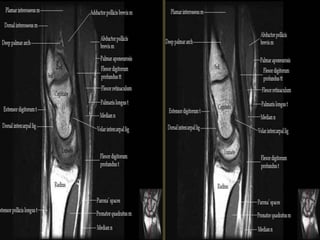

The transverse carpal ligament (short arrows) extends from the hook of the hamate (long

arrow) to the tubercle of the trapezium (arrowhead), forming the floor of the carpal tunnel.

At the radial aspect of the carpal tunnel, the flexor digitorum tendons are arranged in two

rows (separated by dotted line), the profundus tendons deep to the superficialis tendons. The

flexor pollicis longus tendon (star) is positioned at the ulnar aspect of the tunnel, separated

from the flexor carpi radialis tendon (curved arrow) by a ligamentous reflection of the

transverse carpal ligament. The median nerve is indicated (asterisk). - See more at:

http://radsource.us/palmar-bursae-and-flexor-tendon-sheaths/#sthash.mSFX1u0c.dpuf